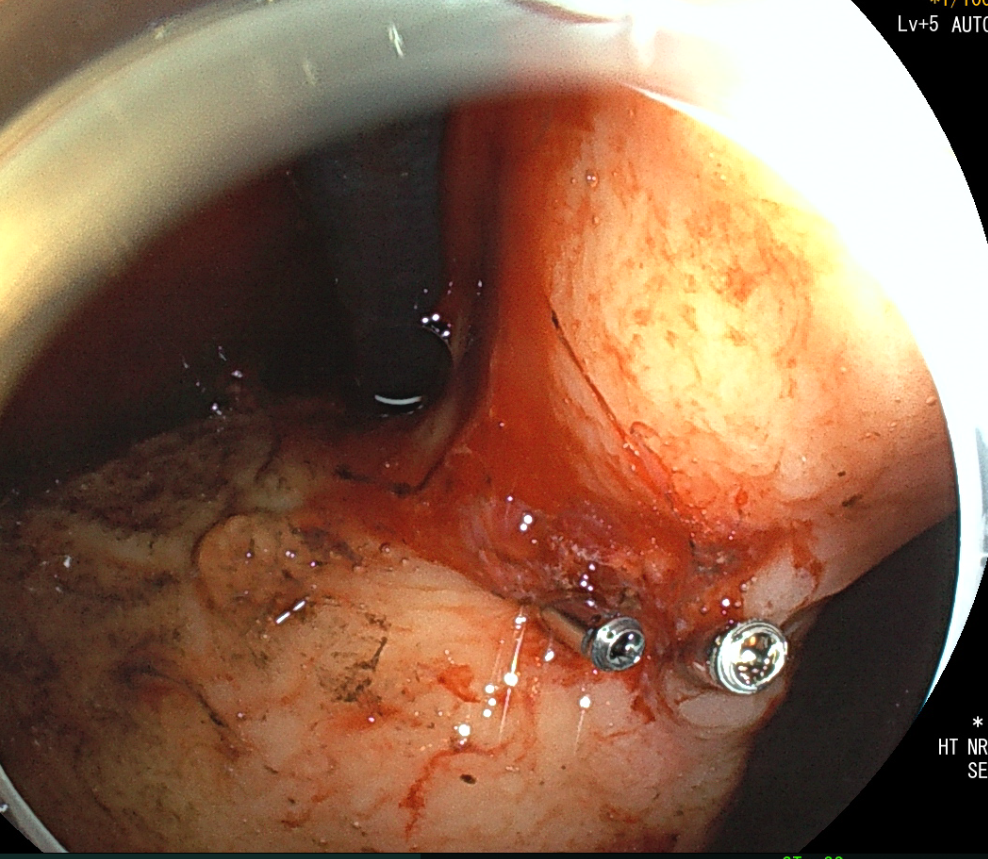

急诊抢救室接诊后立即化验血常规提示血红蛋白61g/L,已临近重度贫血,紧急送往胃镜室,经脾胃肝胆科胃镜检查:胃角见一较深溃疡灶,大小约0.6cm,血管头残留,电凝钳移除血凝块后,见喷射样出血,热凝钳电凝止血后,喷射出血停止,2枚钛夹加固创面,其旁仍见缓慢渗血。

▲ 治疗前

▲ 治疗后